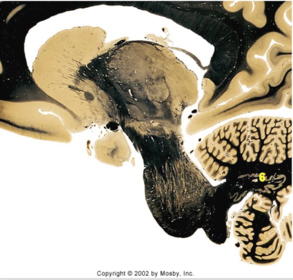

| Head of caudate | |

| Anterior commissure | |

| Thalamus | |

| Substantia nigra | |

| Optic tract | |

| Dentate nucleus | |

| Pons | |

| Longitudinal pontine fibers | |

| Uncus | |

| Superior cerebellar peduncle | |

| Red nucleus | |

| Corticospinal tract (dark) | |

| Pontine nuclei (pale) | |

| Transverse pontine fibers (dark) | |

| Inferior olive | |

| CTT | |

| Medial lemniscus | |

| Nucleus cuneatus | |

| Superior colliculus | |

| Inferior colliculus | |

| Optic nerve | |

| Cerebellum | |

| 4th ventricle | |

| Periaquaductal gray | |

| Dorsal funiculus | |

| MLF | |

| Mammillary body | |

| Pineal body | |

| Posterior commissure | |

| Thalamus |